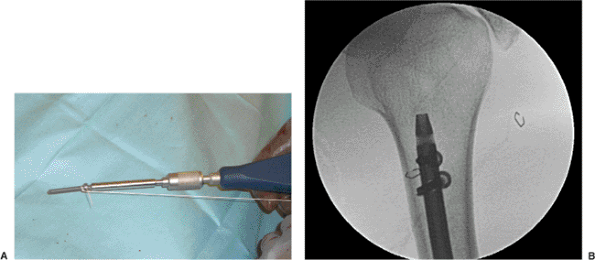

aspect of the olecranon fossa (Fig. 6.6). Using a drill guide, multiple, small, drill holes are made (Fig. 6.7)

that outline the entry portal directly in line with the shaft of the

humerus. These holes are then connected with a large drill bit and

small rongeur to create an oval hole (Fig. 6.8).

ball-tip guide wire is inserted across the fracture site and confirmed

fluoroscopically (Fig. 6.9A) and the canal is sequentially reamed up to an appropriate diameter, usually 1.0 to 1.5 mm

greater than the size of the nail (Fig. 6.9B). While reaming the canal, the surgeon must stay in line with the humeral shaft.

Figure 6.9. A. The guide wire is introduced by hand and (B) the fracture reduction is maintained while reaming.